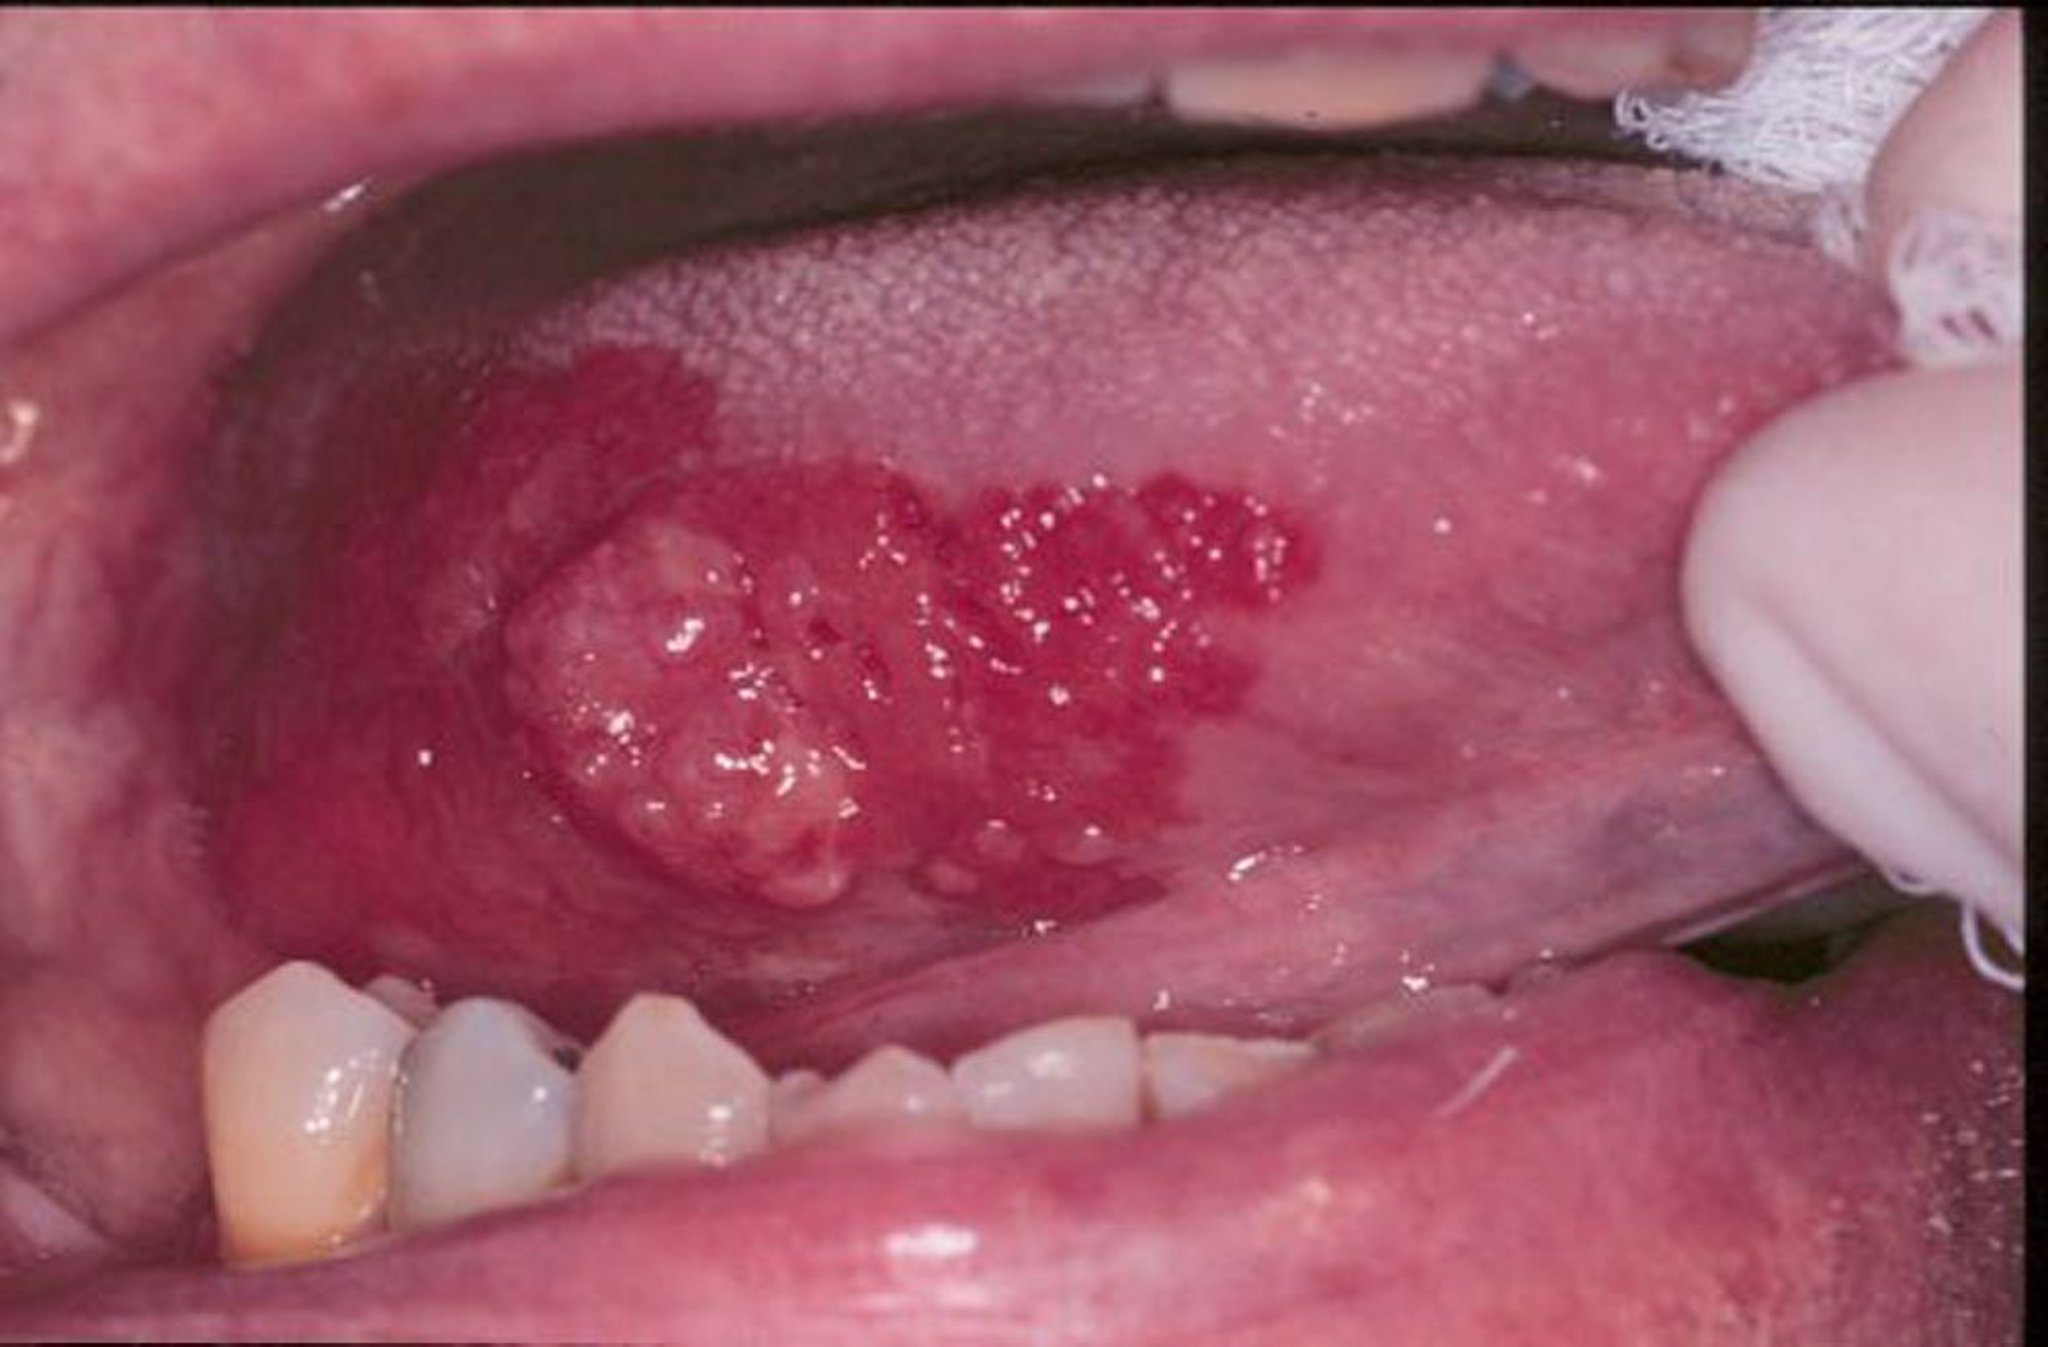

الطلاوة الحمراء والكارسينومة حرشفية الخلايا

الطلاوة الحمراء هي مصطلح عام يُشير إلى القرحات الحمراء، المسطحة، أو المتآكلة المخملية التي تشكلت في الفم.في هذه الصورة، تظهر كارسينومة حرشفية الخلايا محاطة بحواف من الطلاوة الحمراء.

Image provided by Jonathan A.Ship, DMD.